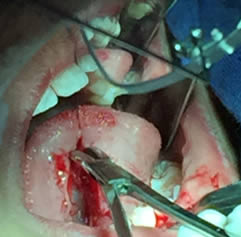

• Se pasa una sutura sin anudar en la punta de la lengua para traccionar la misma y facilitar las maniobras quirúrgicas. Posteriormente se utilizan dos pinzas de mosco, una curva y una recta pinzando el frenillo en su borde superior e inferior para limitar sus bordes. Figuras 3 y 4.

Figura 3. Sutura sin anudar en punta de la lengua

Figura 4. Pinzado del frenillo